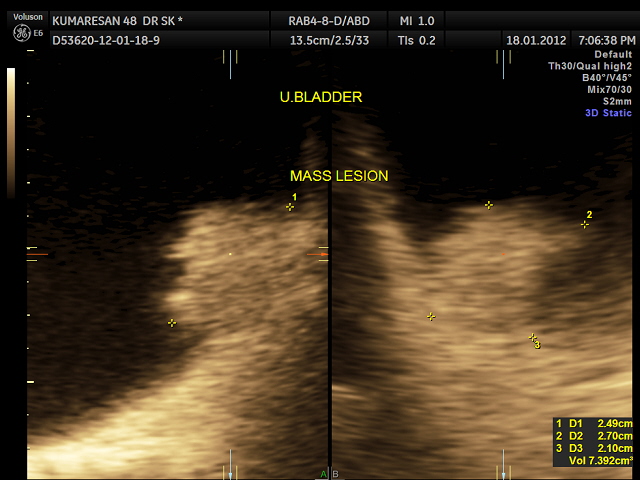

the next is a post void picture showing the mass

the next is a 3 d reconstruction , which shows the prominent median lobe prominence adjacent to the mass.